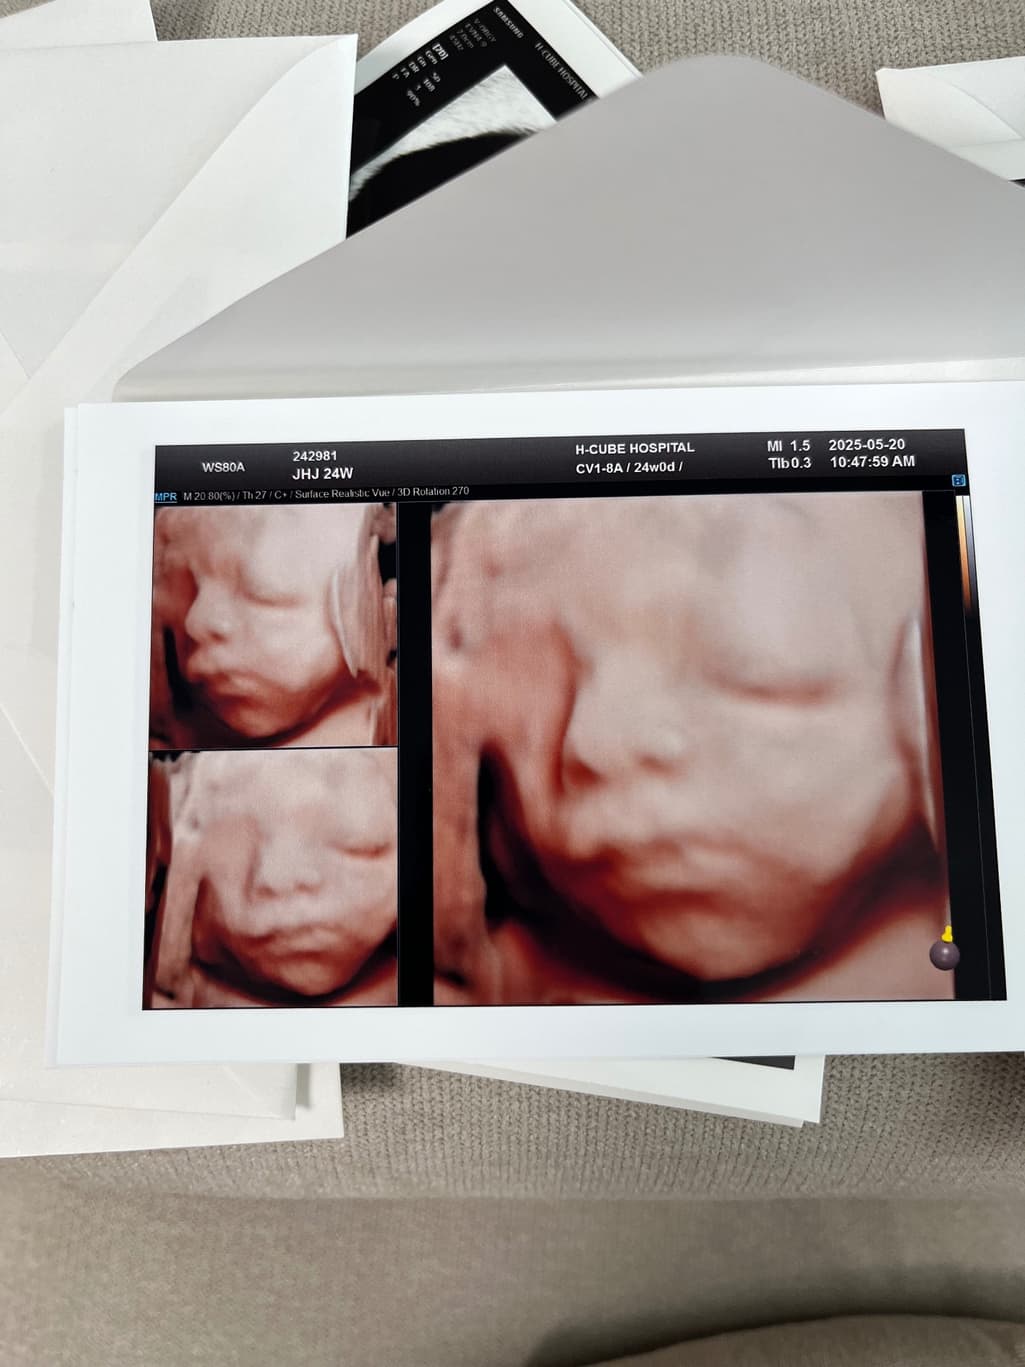

안녕하세요, 사진 순으로 24주차 입체초음파, 그 다음 두 장은 36주차 일반 초음파 사진입니다.

• 1번 째 사진